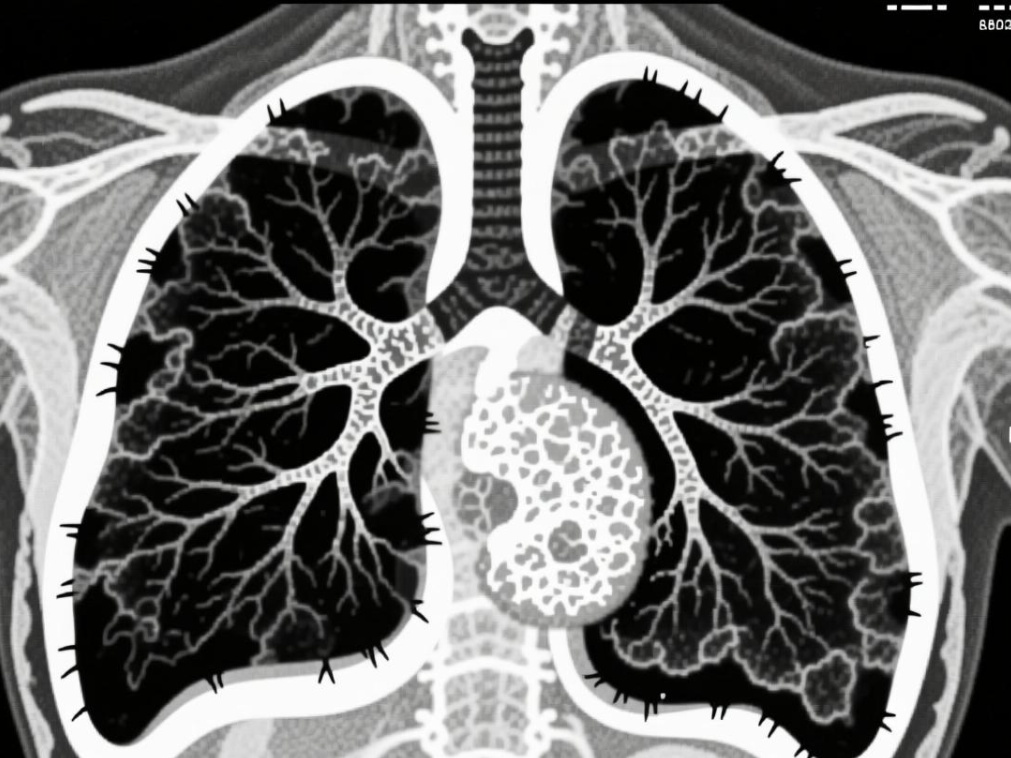

同样是肺癌,有人长期吸烟,有人从不碰烟,却走向了不同结局。肺鳞癌与肺腺癌,发病人...[详情]